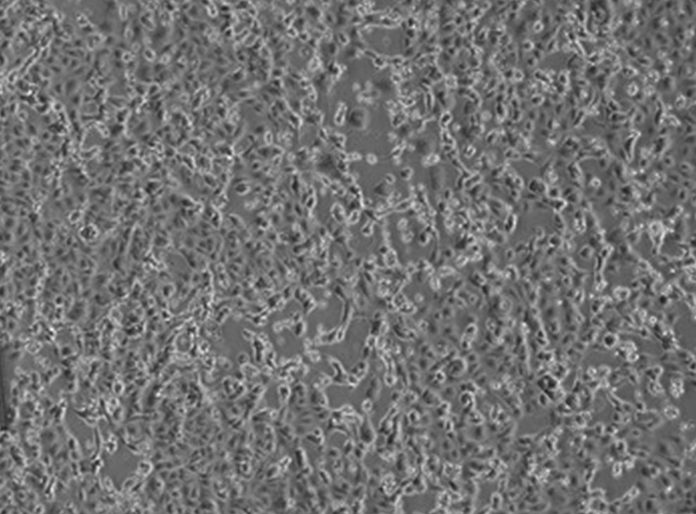

I virologi dell’Istituto Nazionale Malattie Infettive “Lazzaro Spallanzani”, a meno di 48 ore dalla diagnosi di positività per due pazienti in Italia, sono riusciti, primi in Europa, a isolare il virus responsabile dell’infezione.

Avere a disposizione il virus è un passo fondamentale che permetterà di perfezionare i metodi diagnostici esistenti e allestirne di nuovi. Inoltre permetterà di studiare i meccanismi della malattia per lo sviluppo di cure e la messa a punto del vaccino. La sequenza parziale del virus isolato nei laboratori dello Spallanzani, denominato 2019-nCoV/Italy-INMI1, è stata già depositata nel database GenBank, e a breve anche il virus sarà reso disponibile per la comunità scientifica internazionale.